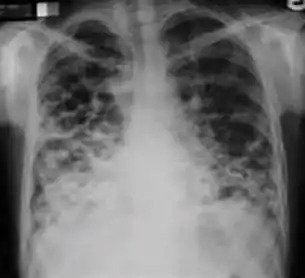

Chest x-ray showing coarse reticulonodular densities on the lower right lung of post-primary pulmonary TB.

3. Nodule with poorly defined margins - Round density within the lung parenchyma, also called a tuberculoma. Nodules included in this category are those with margins that are indistinct or poorly defined (tree-in-bud sign[3]). The surrounding haziness can be either subtle or readily apparent and suggests coexisting airspace consolidation.

Chest x-ray showing nodule with margins that are indistinct or poorly defined (tree-in-bud sign) in post-primary pulmonary TB.